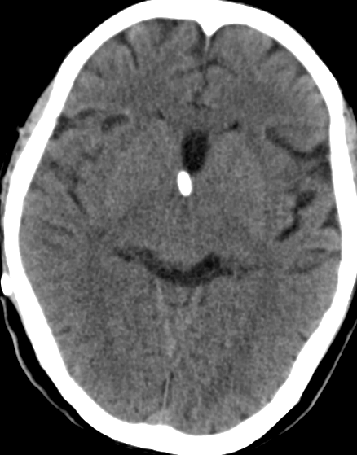

2013-8-12 CT

2013-8-13 调压130——150,头痛症状无明显好转

2013-8-15 出院观察